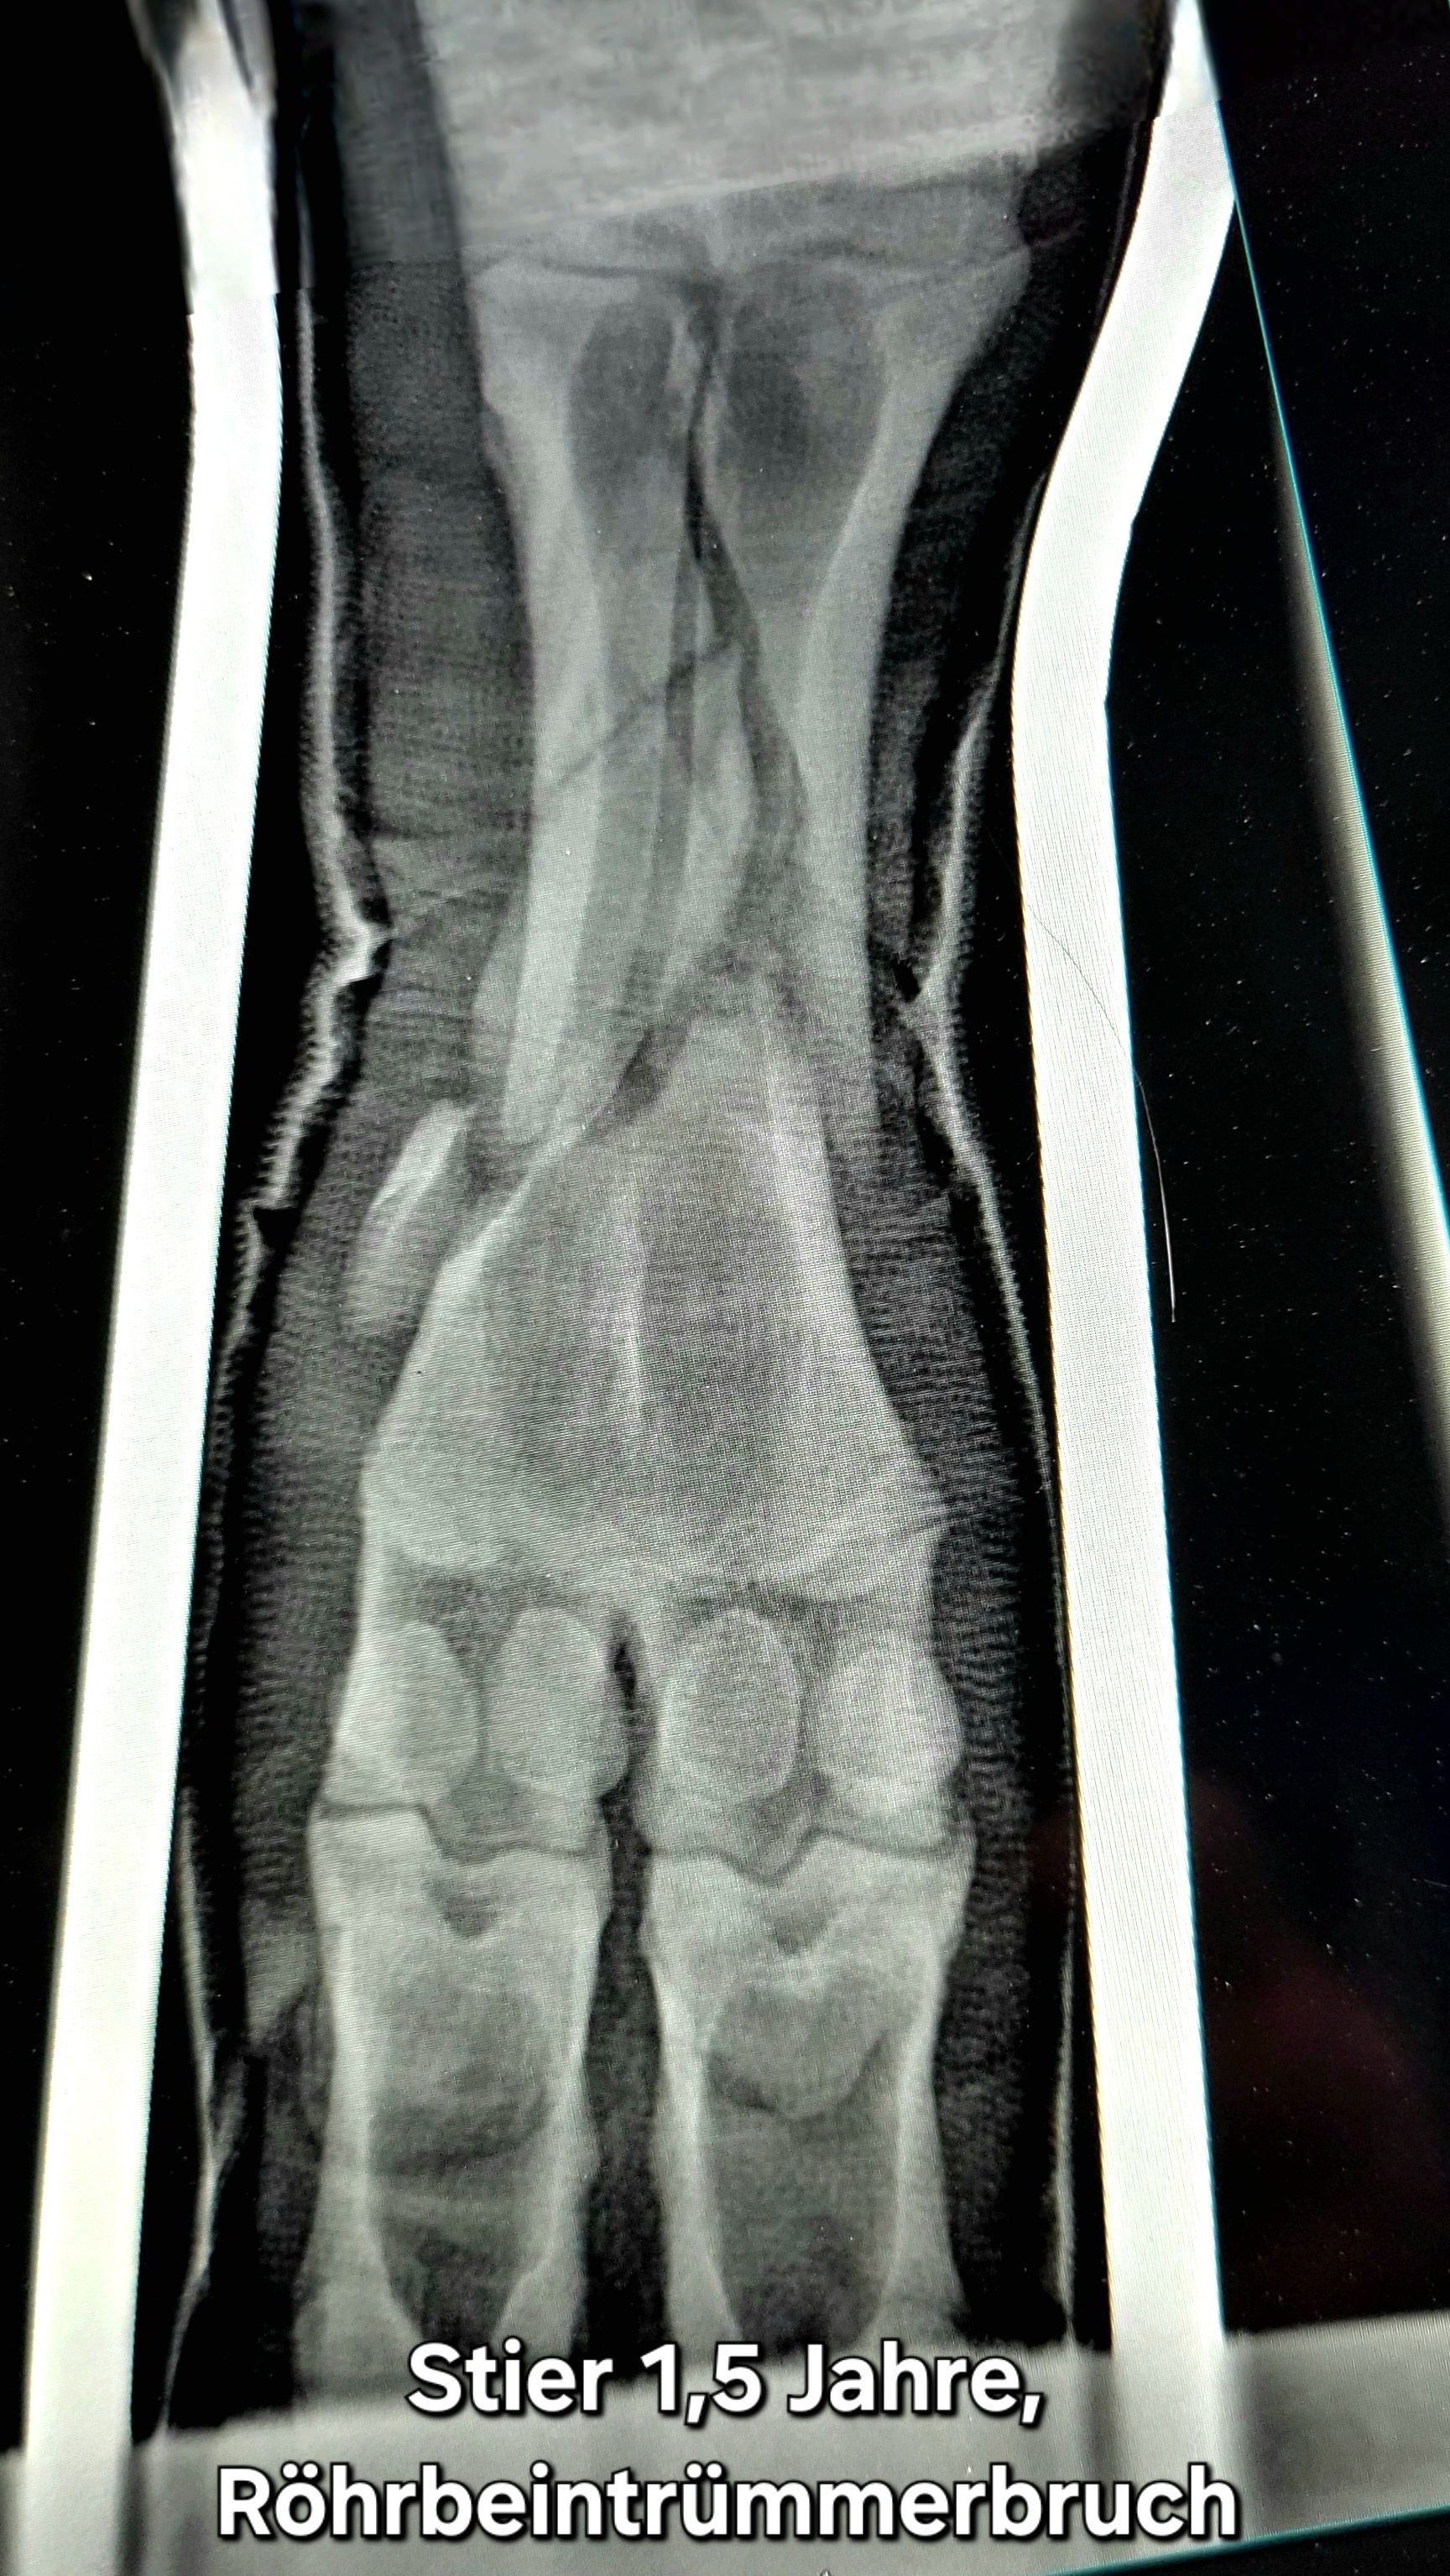

Galerie der Tierarztpraxis für Groß- und Nutztiere Rainer Matzke